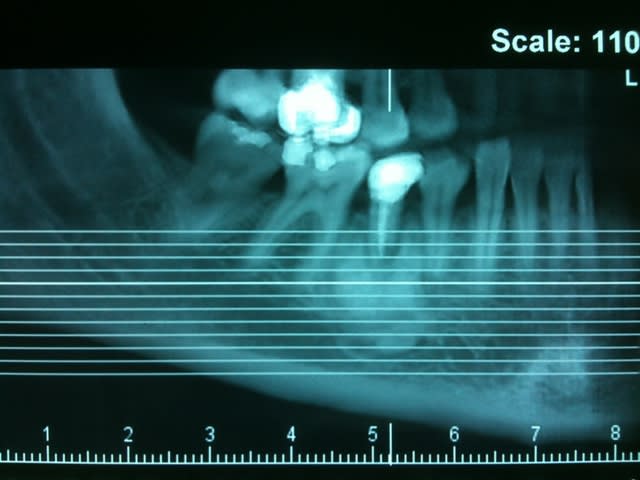

Un confrère savant pourrait il me donner un diagnostic et une CAT concernant le tissu osseux en regard de 45 ?

La racine parait fracturée mais à part une légère douleur à la pression, rien d'autre..

çà semble être une ostéïte condensante...